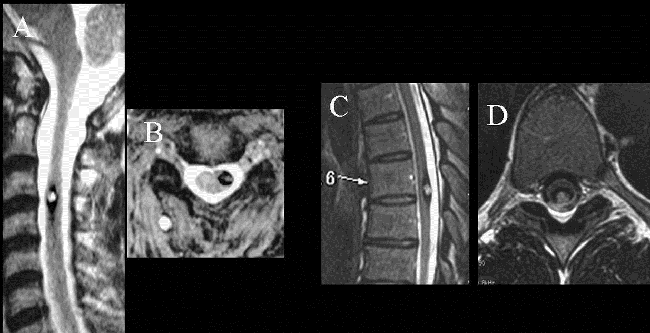

髓内海绵状血管瘤具有类似于其他颅内海绵状血管畸形的出血风险,治疗时应完全切除髓内海绵状血管畸形,以避免残留物复发和再出血。选择微小创伤方法(半椎板切除术),伴随术中超声检查,术中神经生理学监测和细致的显微外科技术,极大切除肿瘤的同时尽可能避免损伤脊柱功能和结构,术后疼痛较轻,患者可尽早进行康复训练,住院时间较短,术后脊柱不稳定性较椎板切除术减少。如今,半椎板切除术已广泛用于切除各种脊髓病变,包括髓内海绵状血管瘤。

半椎板切除术是于1992年最初为世界颅底脑干肿瘤手术大师德国巴特朗菲教授提出的、用于治疗脊柱内部出现的髓外病变。后为了尽可能地实现微创手术,巴特朗菲教授团队使用半椎板切除术作为髓内海绵状血管瘤的一种方法。

半椎板切除术主要根据髓内海绵状血管瘤的定位选择患者位置,患者在俯卧位进行手术。医生在病变区域通过标准方法,即通过背根入口区或中线脊髓切开术接近深部病变。除了精确的定位和脊髓的极佳进入区域,解剖技术可能会影响髓内海绵状血管瘤的手术结果。手术过程中,使用双极钳和微型剪刀来断开引流血管是非常的重要。在确定手术平面后,应以锋利的解剖方式进行病灶表面周围的解剖,以避免正常脊髓组织的损伤。

(A-C)3D-CT扫描显示位于C1-2水平的髓内CM的术后图像。(B)在术中脊髓表面观察到含铁血黄素染色。(C)完全切除髓内CM,显示髓鞘切开的程度

巴特朗菲教授指出,显微镜可用来安全地进行髓内手术切除,当创口最小化并且在精确的肿瘤位置进行切除时,这些损伤通常不会在切除期间出血。术中神经监测对神经外科医生有很大帮助,使其能够更精确地操作并且术后神经功能缺损的风险更低。由于髓内海绵状血管瘤通常位于脊髓的背面,因此,我们证明术中SSEP监测是监测此病手术中脊髓完整性的可靠手段。

参考文献:《Intramedullary cavernous malformations: Clinical features and surgical technique via hemilaminectomy》L.G. Biana,*,H. Bertalanffy b,Q.F. Suna,Jian-Kang Shena